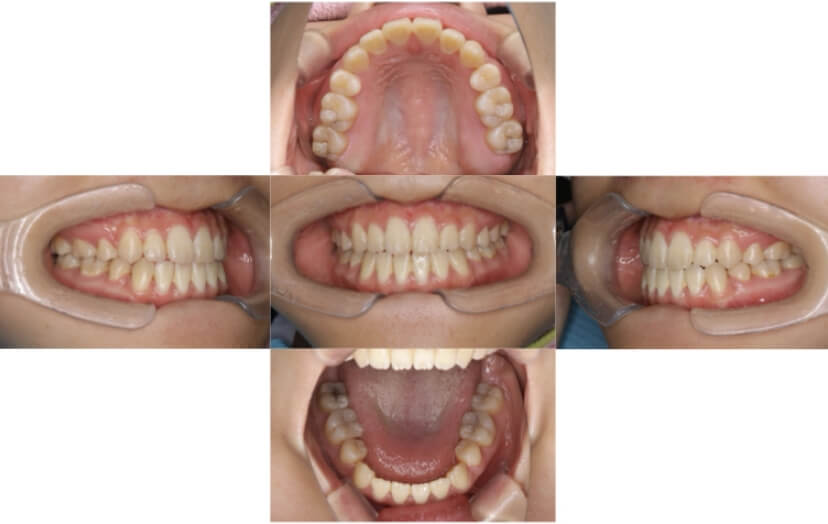

AFTER

上下顎叢生(上下の前歯のガタガタ)のケースです。

装置はラビアル(上下表側)で、右上以外の小臼歯を3本、右上は犬歯の抜歯を行っています。抜歯したスペースを使って、上下の前歯の後方移動と叢生(ガタガタ)の改善を行っています。

主訴 八重歯を治したい。

年齢・性別 27歳 女性

お住まいの地域 東京都港区

治療方針 抜歯スペースを利用して上下前歯の叢生(ガタガタ)の改善

抜歯部位 上顎右側犬歯、上顎左側第一小臼歯、下顎両側第一小臼歯

使用装置 ラビアル(上下表側)、顎間ゴム

治療期間 3年3か月

治療回数 25回

リテーナー クリアリテーナー